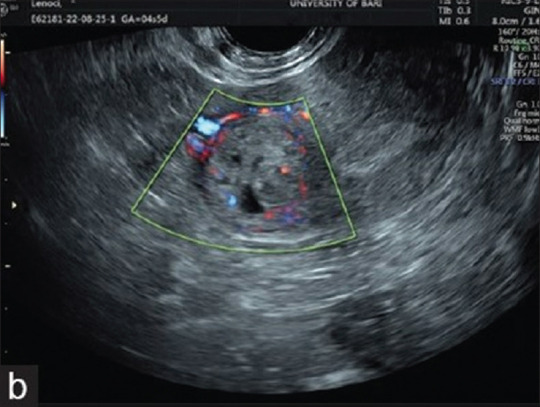

Regarding Cornual Pregnancy.

关于双角妊娠。